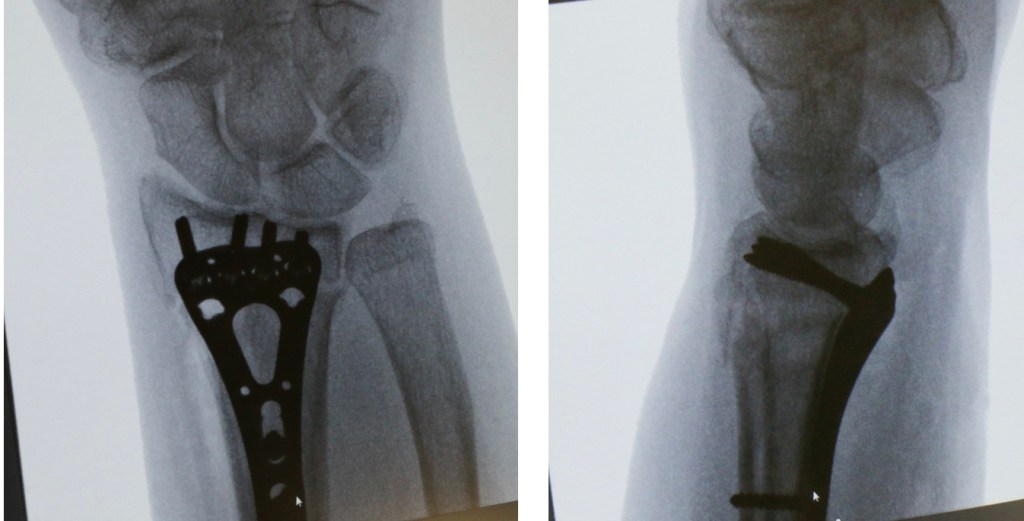

– An operation. At operation, the surgeon will again manipulate the bones back into position and fix them there with either some wires (these wires are a bit like barbeque skewers – they are relatively stiff with a pointed end to drill into the bone), or a plate. If a bone plate is used, a wound is made over the palm side of the wrist, and the plate inserted under the muscles and tendons.

Although surgery stabilises the bones and usually allows early movement, there are risks involved with surgery, and you can read more about these here. Although the surgeon will aim for a perfect position of the bones, this is not always achieved, and occasionally the fixation fails to hold the position of the bones. Late problems associated with the use of bone plates include tendon irritation or rupture, and the risks and benefits should be discussed with the surgeon before having this type of operation.